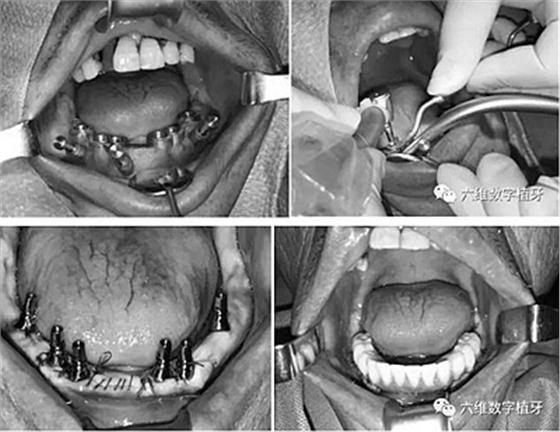

導(dǎo)航手術(shù)過程照片

通過術(shù)前精確的設(shè)計,避開了患者骨壁較薄需要做骨劈開的區(qū)域,避免了大翻瓣造成較大創(chuàng)傷,大大提高了患者的舒適度。

全程手術(shù)采用小翻瓣微創(chuàng)種植,選擇初期穩(wěn)定性較好的植體進(jìn)行即刻負(fù)重。整個手術(shù)從開始到最終戴上臨時牙,只花費2個小時的時間,就讓患者恢復(fù)了完美笑容。數(shù)字化種植為醫(yī)生和患者帶來不一樣的感受!